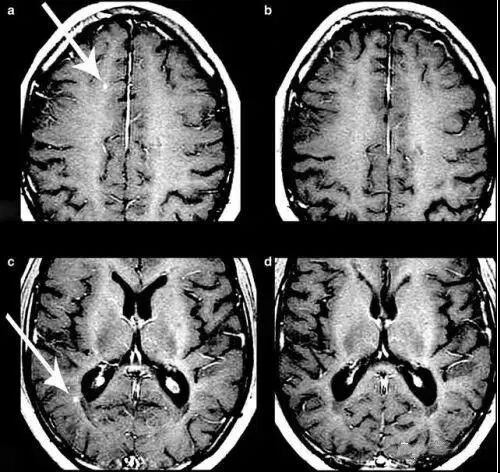

2012年,《柳叶刀·神经病学》上发表的一项研究显示,间充质干细胞用于调理继发性、进行性、多发性硬化症是安全的,调理后患者视力得到改善,视神经面积增加。